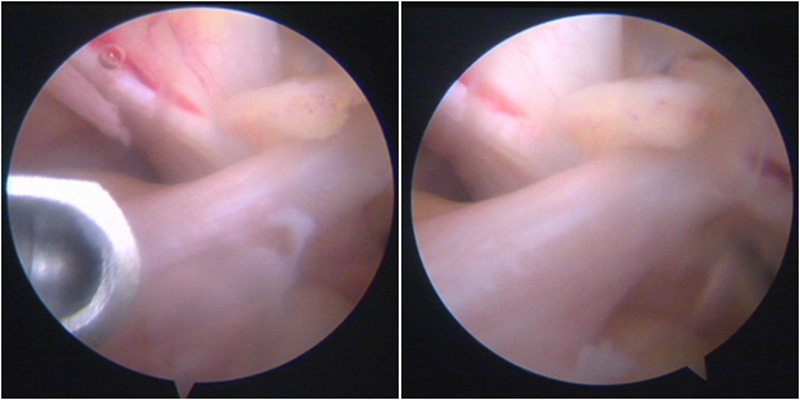

镜下显示ACL残束

内侧半月板

外侧半月板